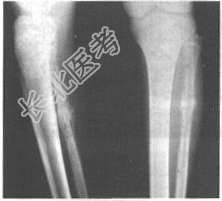

- [材料题] 患者,男,17岁。因左下肢疼痛2个月入院,查体:左小腿中段局部肿胀,组织增厚较硬,有压痛,局部皮温稍高。体温38.2℃,实验室检查:WBC:13.8×10¹²/L,N:78%;X线平片见下图。

- 简答题1、根据以上临床资料及影像学检查,需要考虑哪些疾病?

- 简答题2、该病最可能的诊断为?

- 简答题3、急性骨髓炎与尤因肉瘤有哪些主要的鉴别点?